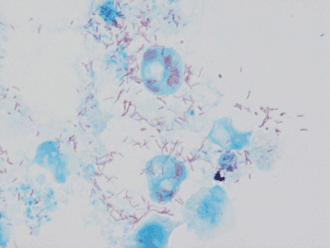

Rickettsia conorii é uma bactéria de vida intracelular obrigatória, que atua como agente etiológico da febre escaronodular, uma febre maculosa do grupo B.

As riquétsias são organismos pleomórficos, geralmente cocobacilos. São Gram – negativos de 200 a 500 nm por 800nm de diâmetro. Têm uma parede celular, com lipoproteínas e peptidoglicano. Coram pelo método de Gimènez.

São incapazes de crescer na ausência de células vivas do hospedeiro. Instalam-se em células endoteliais.